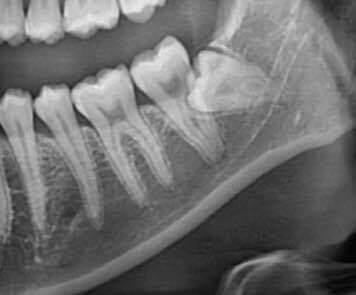

매복 사랑니 발치

매복 사랑니가 위험한 이유

비정상 각도·방향 → 옆 어금니 손상·충치

잇몸 염증·심한 통증 → 부기·발열·개구 장애

신경관 근접 → 방치 시 감각 이상 위험

매복 사랑니 발치, 왜 플란트구강악안면외과 치과일까요?

1. 10,000건 이상의 압도적인 임상 경험

저희 치과의 의료진은 대학병원에서의 풍부한 경험을 바탕으로 10,000건 이상의 사랑니 발치 케이스를 성공적으로 진행했습니다.